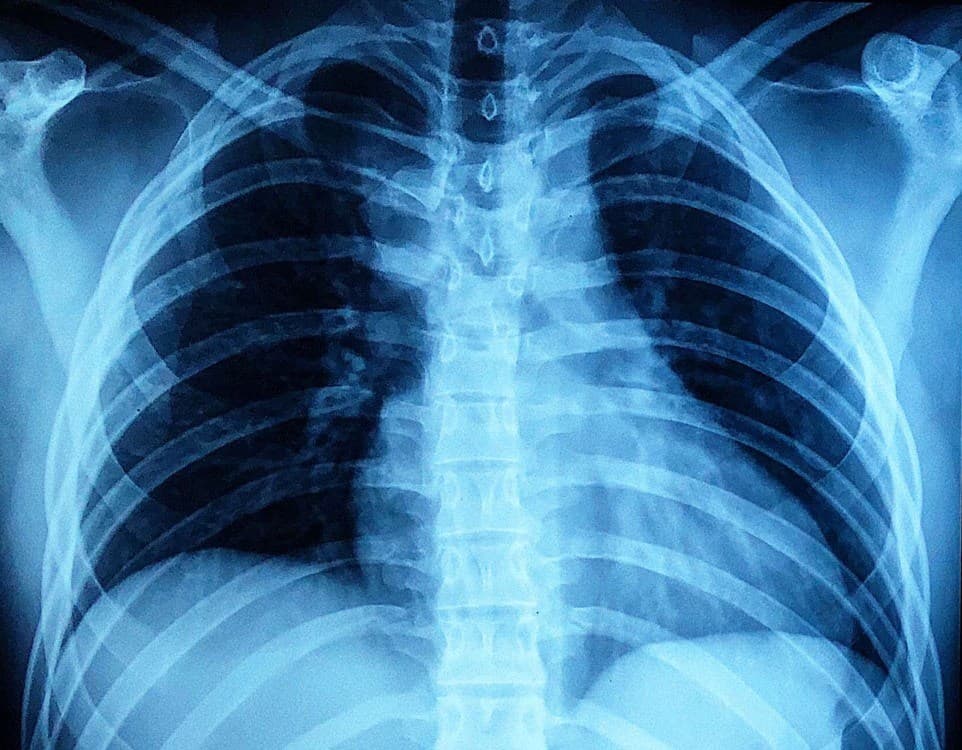

Trật khớp ức đòn

» Thông tin: Nam giới – 23 tuổi.

» Lâm sàng: Chấn thương vai phải.

# Trật khớp ức-đòn phải ra sau.